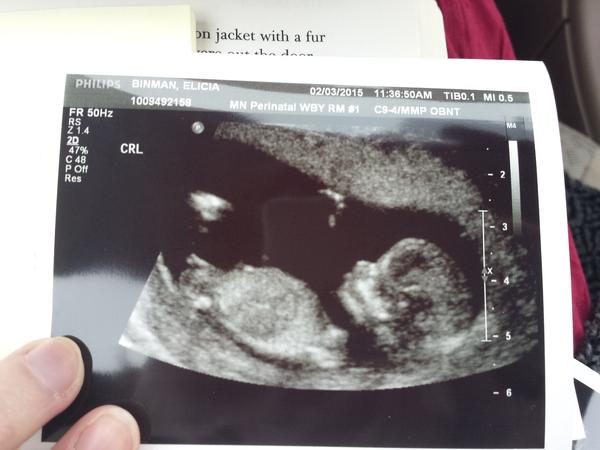

Ultrazvuk - holka nebo kluk?

Ahoj holky jsem v 17 týdnu a miminko je tak akční,že nám řekli 1* holku na screeningu ve 12 týdnu(mimi bylo ukázkové klidné) a v 16 týdnu paní dr řekla že asi kluk (mimi bylo moc akční fotku mam jen jak je otočené jinak se to nedalo 😂)...A další kontrolu mam až za mesic...Co myslíte? 🙂 Každý mi dle fotky říká holku